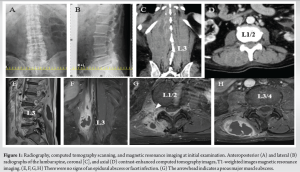

An 83-year-old man was admitted to the department of urology at our hospital for further examination due to urinary retention in the past month. He had no history of lumbar puncture but had a medical history of benign prostate hypertrophy and diabetes mellitus. Fever and elevated C-reactive protein (CRP) levels indicated a diagnosis of pyelonephritis. Methicillin-resistant Staphylococcus aureus (MRSA) was confirmed through blood and urine cultures, and tazobactam piperacillin was changed to trimethoprim-sulfamethoxazole and minocycline based on antibiotic susceptibility. The patient experienced right back pain during physical activity 2 months before admission and was referred to our department on day 8 after admission. On initial examination, his body temperature was 37.2°C; swelling, local heat, fluctuation, and tenderness were detected in the right paraspinal muscle of the lumbar region. Right low back pain develops during forward movement, extension, and bilateral bending. The patient reported no nocturnal pain or neurological deficits. On admission, his white blood cell count was 27,500/μL and the CRP was 17.8 mg/dL, hemoglobin A1c was 12.0%, and blood glucose level was 305 mg/dL. A urologist consulted a diabetologist. Insulin-fortified therapy was initiated, and the blood glucose levels were well controlled. Plain lumbar radiographs revealed sciatic scoliosis on the right side and contrast-enhanced computed tomography (CT) revealed a low-absorption area with rim enhancement in the right paraspinal muscle (Fig. 1a, b, c, d). Magnetic resonance imaging (MRI) of the spine revealed a low-intensity lesion on T1-weighted images compared with the muscle intensity, with rim enhancement extending into the right psoas major muscle through the interspaces of the costal processes at the L1/2 level. There were no signs of an epidural abscess or facet infection (Fig. 1e, f, g, h).